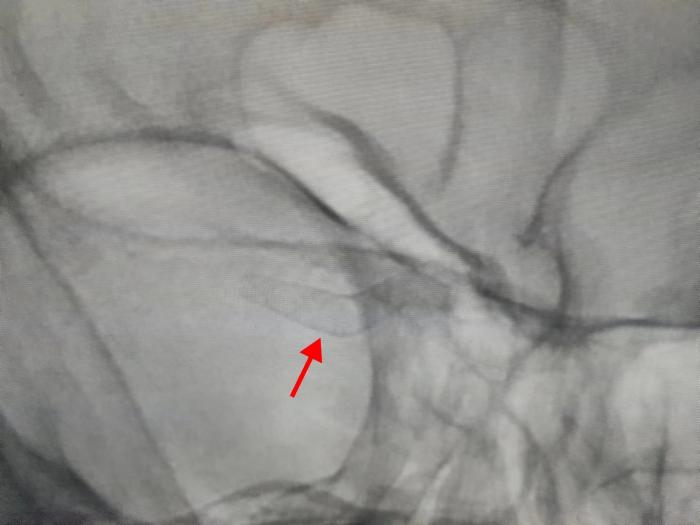

入院后,通过对刘女士做了进一步检查,并完善了DSA脑血管造影,周定中发现患者右侧大脑中动脉M1段分叉处确实存在动脉瘤,更糟糕的是刘女士的动脉瘤呈“多发性”,病情复杂。周定中介绍,“刘女士的瘤颈较宽,传统术后宜复发,并且瘤体呈不规则形态,破裂风险大,瘤体位置还处于血管分叉处,手术中容易误伤其他重要血管,情况非常棘手!”

完善术前准备后,周定中带领介入血管外科手术团队在麻醉科的紧密配合下,经过精细的术中操作,顺利进行了右颈内多发动脉瘤血流导向密网支架置入术。手术顺利完成,术中仅用时1个多小时,无任何并发症和不适。术后患者头晕头疼、四肢无力感消失,术后第四天,刘女士高兴地康复出院。